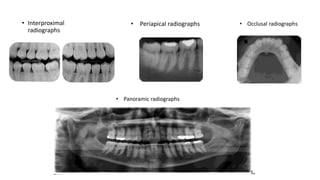

• Interproximal

radiographs

• Periapical radiographs • Occlusal radiographs

• Panoramic radiographs